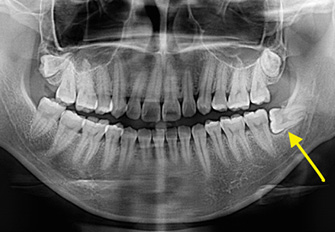

Fig 1 : Pre-operation x-ray shows impacted wisdom tooth

Fig 2 : Pre-operation